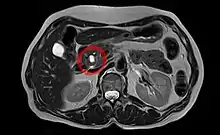

| Intraductal papillary mucinous neoplasm in magnetic resonance imaging. | |

Intraductal papillary mucinous neoplasm (IPMN) is a type of tumor that can occur within the cells of the pancreatic duct. IPMN tumors produce mucus,[1] and this mucus can form pancreatic cysts.[2] Although intraductal papillary mucinous neoplasms are benign tumors, they can progress to pancreatic cancer.[1] As such IPMN is viewed as a precancerous condition.[3] Once an intraductal papillary mucinous neoplasm has been found, the management options include close monitoring and pre-emptive surgery.